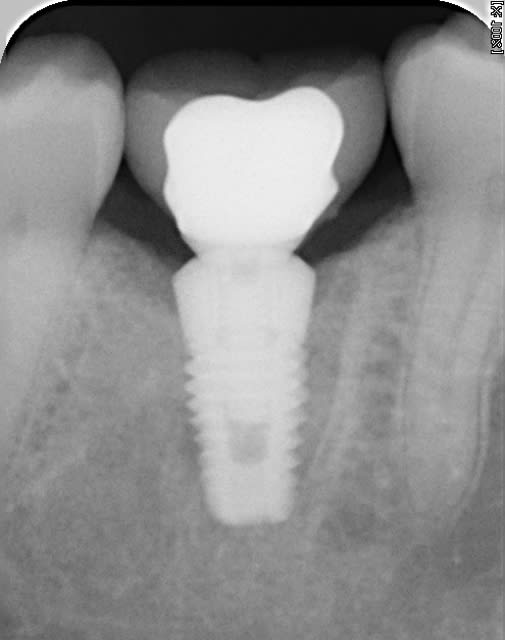

bon les pièces jointes d'alhoun.

décidément aussi nul en endo qu'en internet, et ton implant il est de traviole;)

dans la même philosophie de connectique

Easyimplant mjxotp - Eugenol

Rvg easy briwxo - Eugenol

Ok j'ai compris. Par contre, sur la radio l'implant a l'air d'être conique sur toute sa hauteur, c'est une illusion d'optique où il est vraiment comme ça, je ne le vois pas sur le site d'Astra ?

tu parles de celui de growler?

c'est normal c'est pas un astra, c'est un easy implant, mais il est pas conique tout le long il me semble.

çà doit être une déformation du cliché, regardes bien le premier cliché avec le pilier de cicatisation: on voit bien la partie cylindrique puis l'évasement.